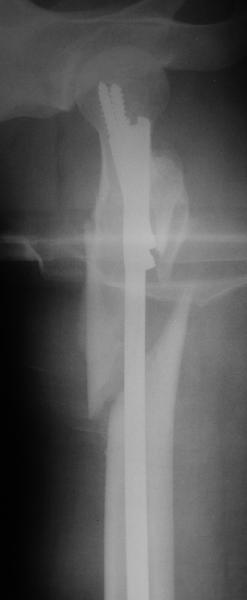

Оперировали вчера. Не сказать, что все прошло гладко - вертельная область была расколота и в сагиттальной, и во фронтальной плоскости, гвоздь попал в перелом и сместился кзади, что заметили уже после введения винтов, пришлось все извлечь и переставить. Снимки в приложении. Буду признателен за комментарии.

Если честно, мне не нравится стояние отломков

проксимального отдела. На мой взгляд причина в недостаточной осевой тракции сегмента перед этапом дистального блокирования. Если это действительно так, я бы попробовалудалить дистальные блокирующие винты, дать осевую тракцию(дистрактор, ортопедический стол, др.) и повторное дистальное

блокирование.

уважаемый А.Ч.! Не уверен, что отломки сопоставлены хорошо. Особенно плохо лбстоят дела с малым вертелом. Клинический исход по-видимому будет неудовлетворительным.

Спасибо на добром слове ;-)

Похоже, не дотянули мы длину около 1 см - будем надеяться, что с учетом тяжелого перелома пятки на этой же стороне и перелома таза не это станет доминирующей проблемой. У пациентки скоро 2 месяца после операции, надеюсь, появится - сделаем снимки, глянем. Насчет несопоставления малого вертела - пожалуйста, поясните, какими бедами это чревато.